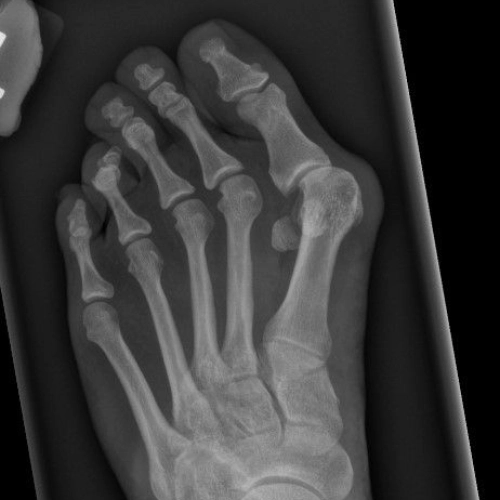

Tailor’s bunion treatment for pain and deformity on the outer side of the footTailor’s bunion treatment for pain and deformity on the outer side of the foot

Bunion treatment to correct toe alignment and relieve foot painTailor’s bunion treatment for pain and deformity on the outer side of the foot

Tailor’s bunion treatment for pain and deformity on the outer side of the foot06-